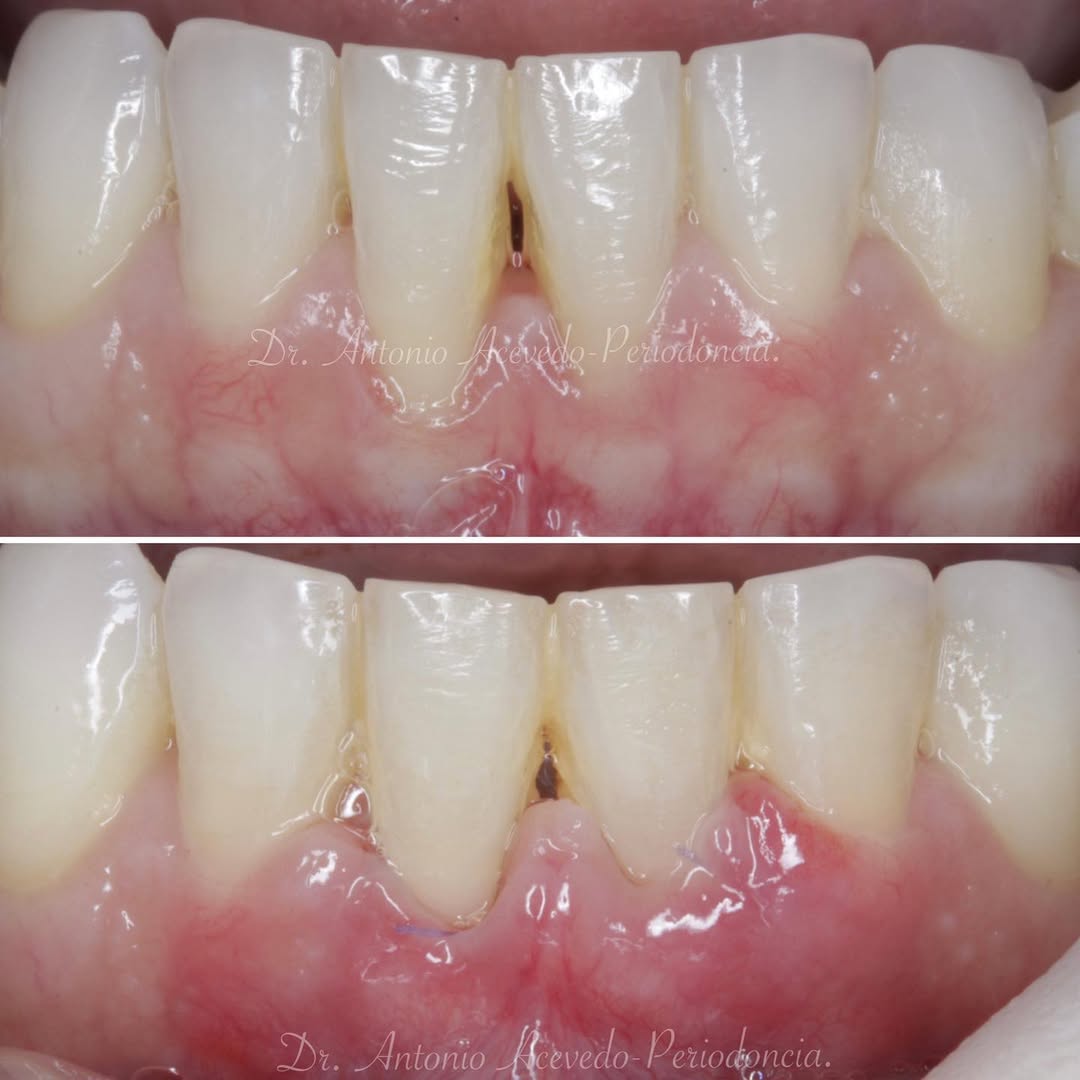

Los problemas estéticos de una sonrisa no se ciñen sólo a los dientes eso lo sabemos todos. Por eso un curso de Perio-Estética, es fundamental para poder abordar casos de Estética y solo a través de un correcto diagnóstico previo podremos realizar un adecuado plan de tratamiento, muchas